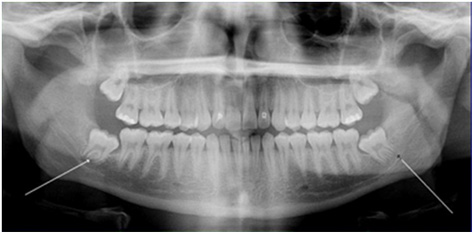

Dưới đây là một số hình ảnh răng khôn mọc ngầm gây khó chịu cho khách hàng đã được xử lý tại Bệnh viện Đa khoa Hoàng Tuấn.